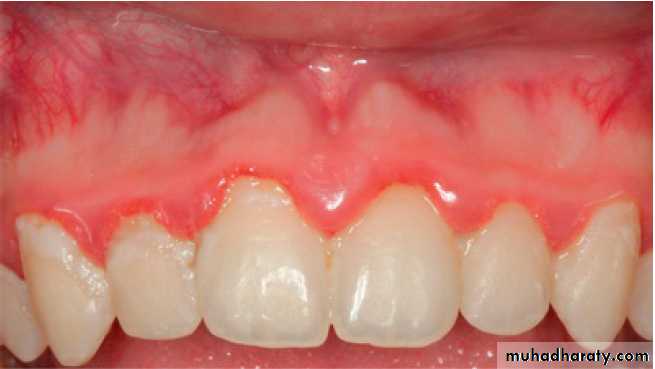

Examination of the Periodontium:

*1st dryness of the gingiva.

*Inspect the color of gingiva,(red spongy texture smooth, glossy)or pale & firm or bluish gray

*Bleeding on probing (only 30% of sites with bleed will go on to lose attachment )

*Pressure by index finger

*Localized or generalized , marginal or diffused , edematous or fibrotic.